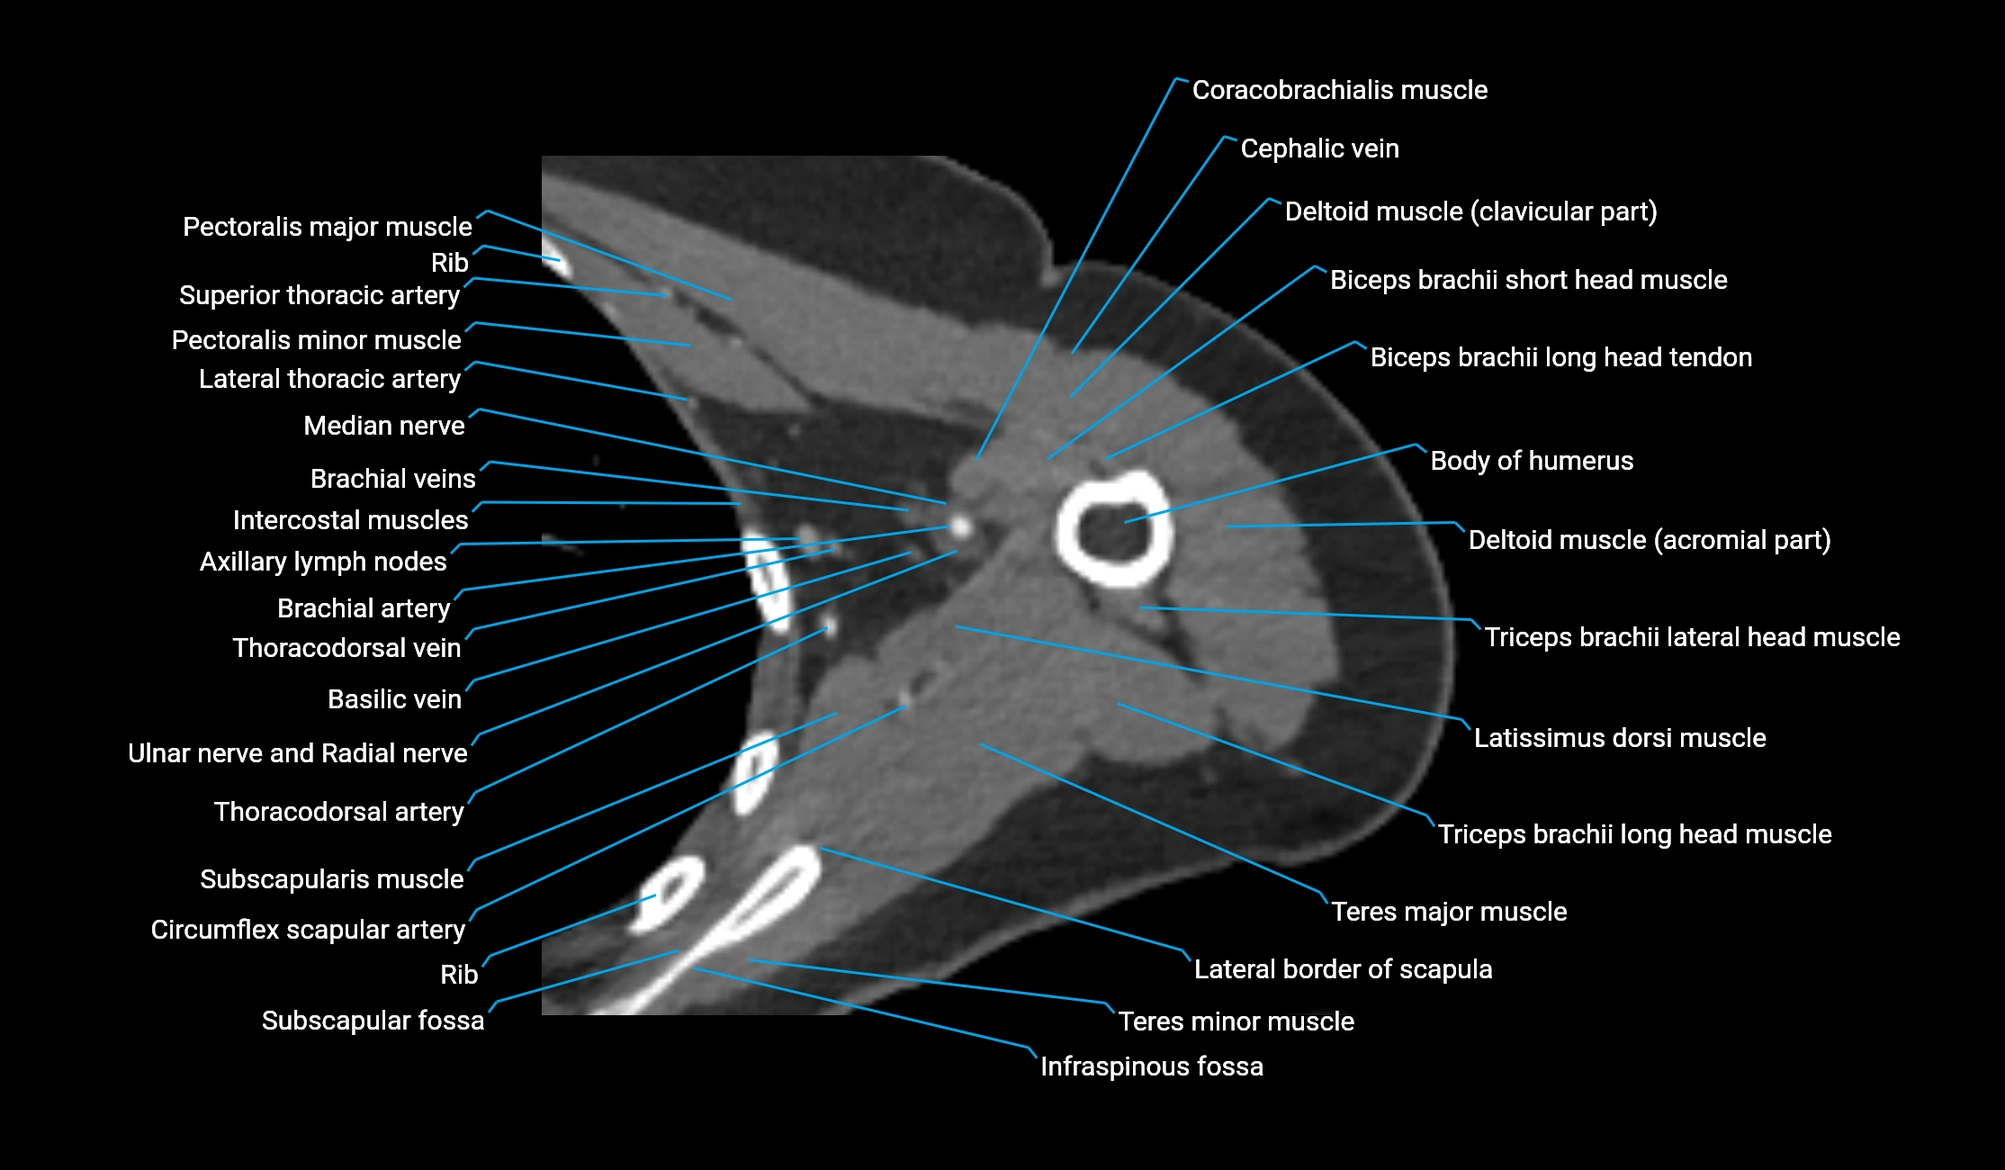

- Axillary lymph nodes

- Basilic vein

- Biceps brachii muscle

- Body of humerus

- Brachial artery

- Cephalic vein

- Circumflex scapular artery

- Clavicular part of deltoid muscle

- Coracobrachialis muscle

- Infraspinous fossa

- Lateral border of scapula

- Lateral head of triceps brachii muscle

- Long head of triceps brachii muscle

- Median nerve

- Pectoralis major muscle

- Pectoralis minor muscle

- Subscapular fossa

- Subscapularis muscle

- Teres major muscle

- Teres minor muscle

- Thoracodorsal artery

- Triceps brachii muscle